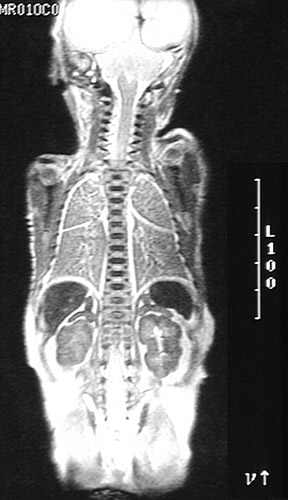

The T2 weighted MRI scan in coronal view seen here demonstrates the normal fetal adrenal above the kidney. Note the size ratio here of 1:8 near term, compared to the adult ratio of 40 or 50:1.